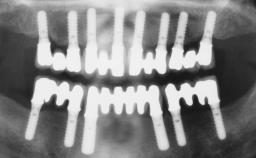

# of Teeth 3

# of Implants 3

Bone Augmentation Horizontal|Staged|Vertical

Augmentation Materials Autogenous chips|Autogenous block(s)